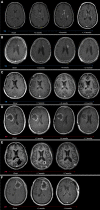

Results: We identified 64 cases of mostly (80%) biopsy-confirmed PP (n = 27) and TN (n = 37), comprising 137 ROIs in total V体育ios版. Median time of onset for PP and TN was 1 and 11 months after RT, respectively. Clinically, PP occurred more frequently during active antineoplastic treatment, necessitated more steroid-based interventions, and was associated with glioblastoma (81 vs. 40%), fewer IDH1 mutations, and shorter median overall survival. Radiographically, TN lesions often initially manifested periventricularly (n = 22/37; 60%), were more numerous (median, 2 vs. 1 ROIs), and contained fewer malignant elements upon biopsy. By contrast, PP predominantly developed around the tumor resection cavity as a non-nodular, ring-like enhancing structure. Both PP and TN lesions almost exclusively developed in the main prior radiation field. Presence of either condition appeared to be associated with above-average overall survival. .

Conclusion: PP and TN occur in clinically distinct patient populations and exhibit differences in spatial radiographic pattern. Increased familiarity with both conditions and their unique features will improve patient management and may avoid unnecessary surgical procedures. VSports最新版本.